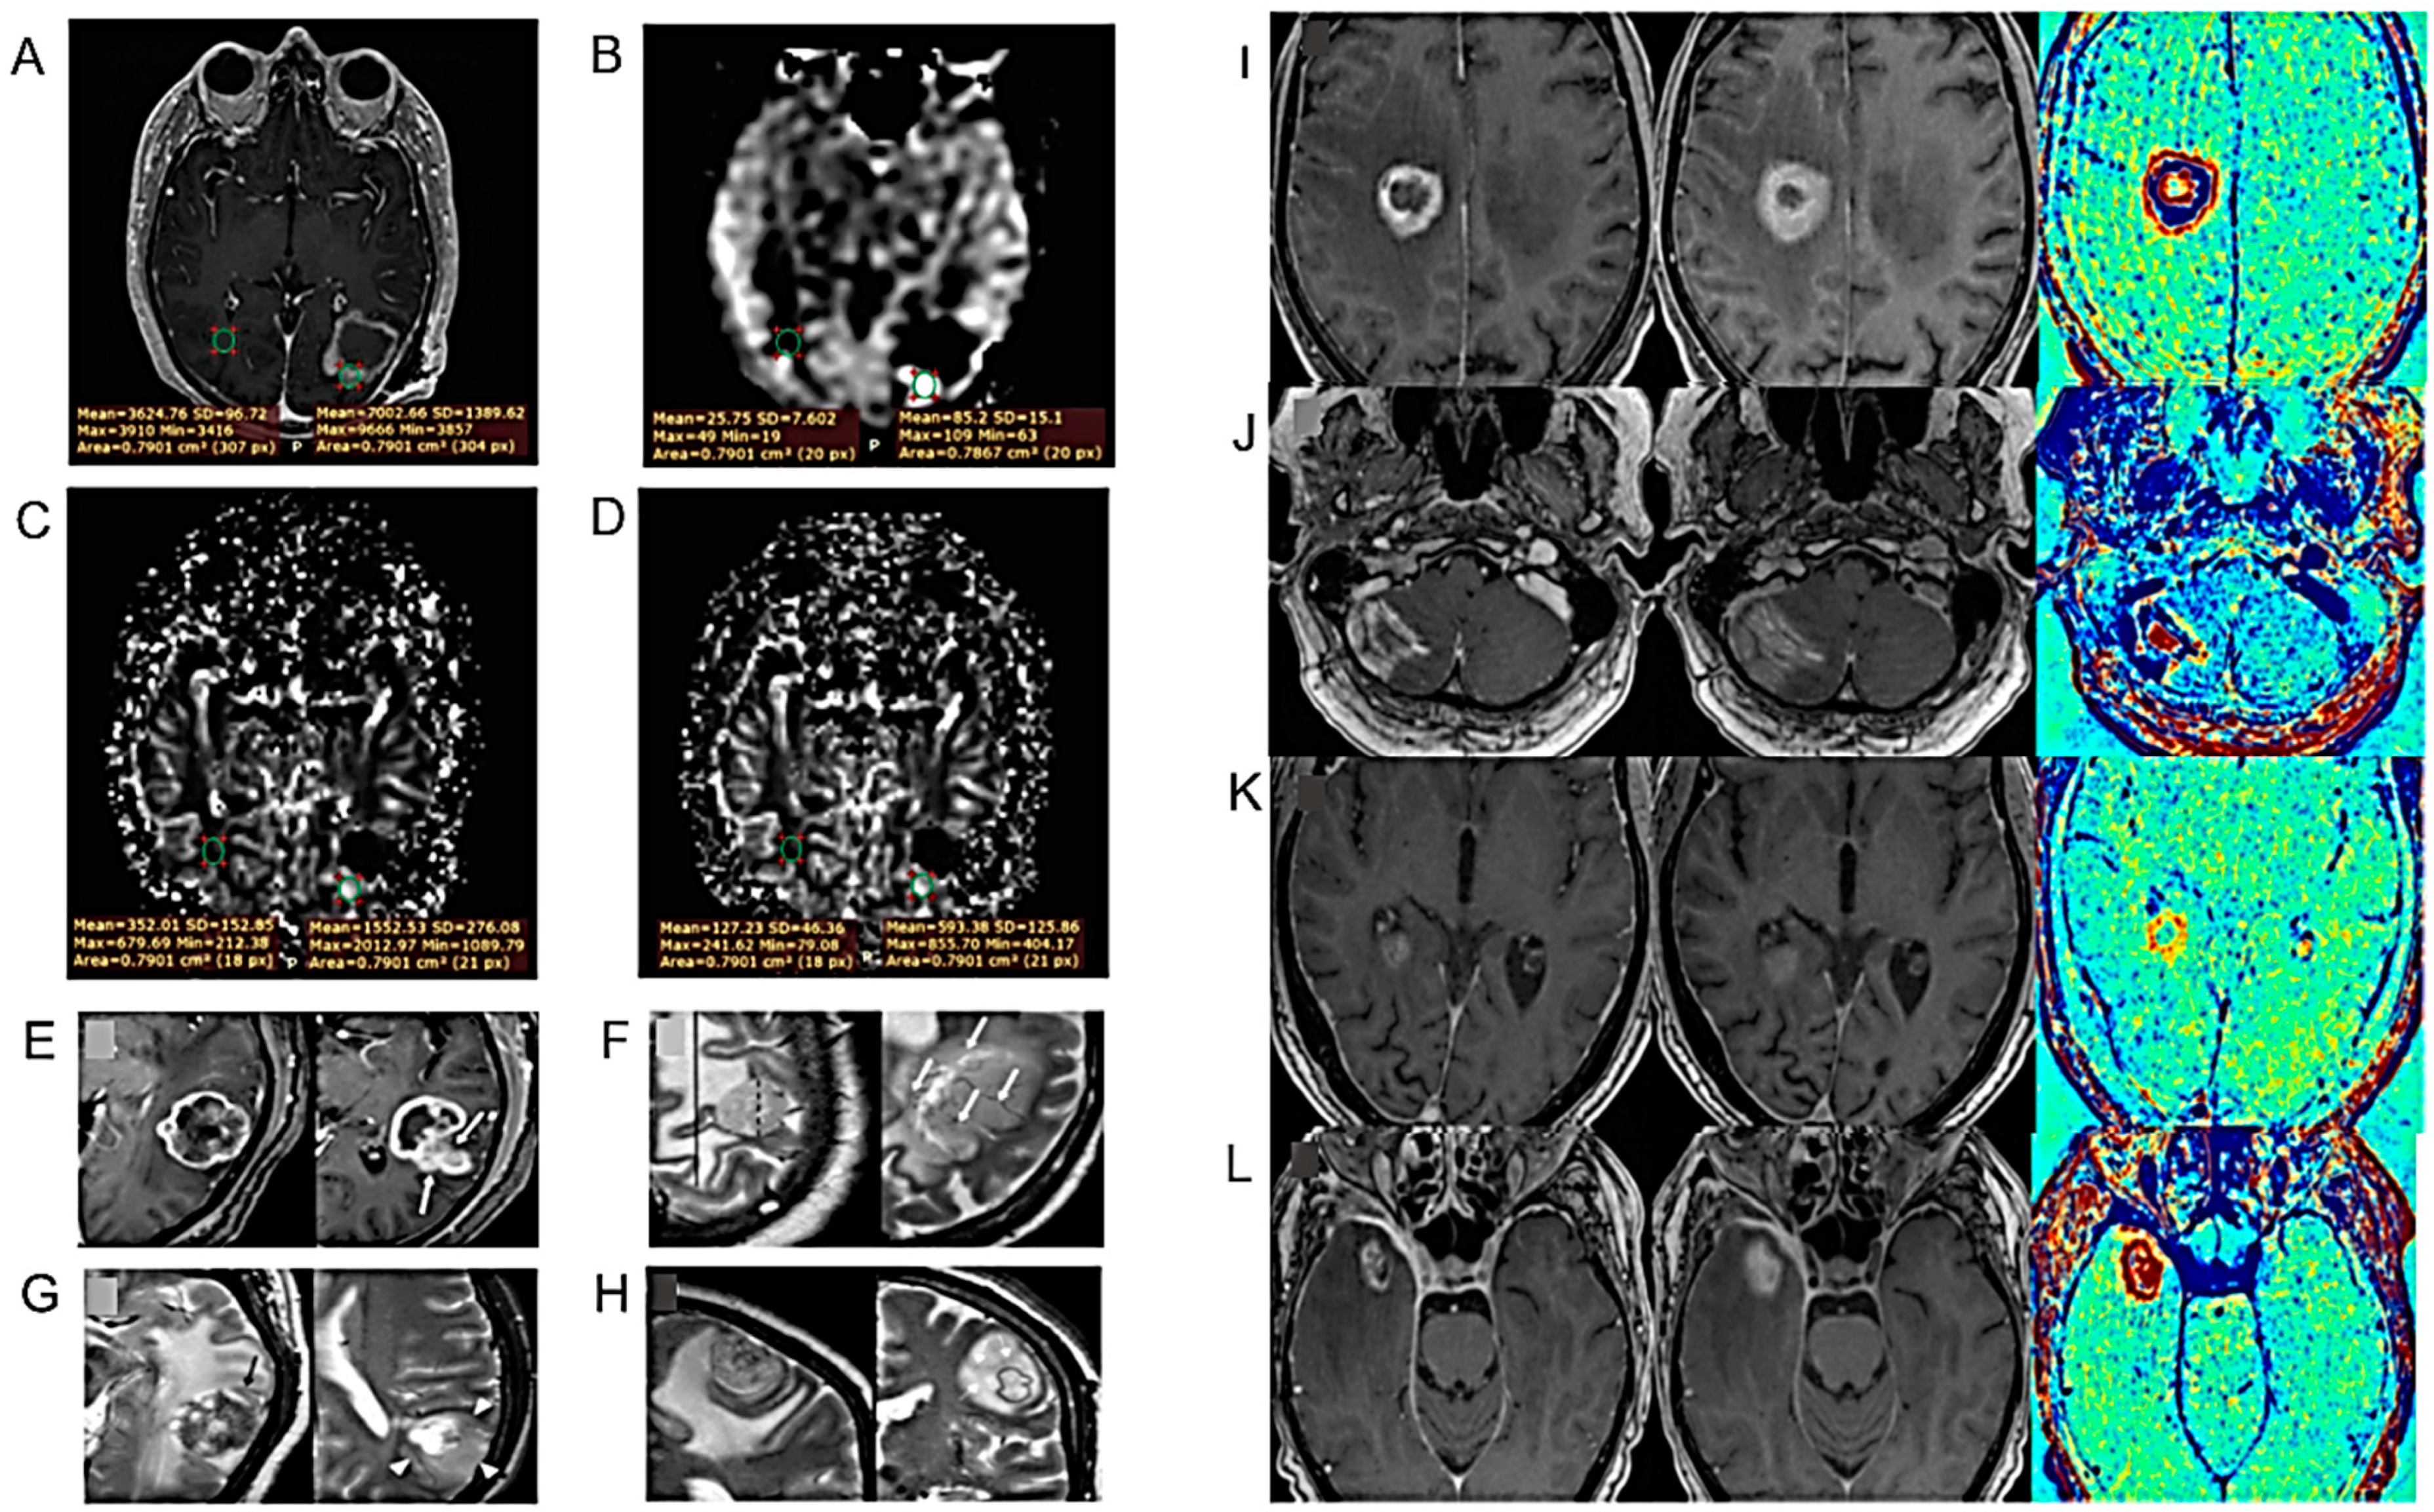

| APTw MRI imaging shows good scan–rescan reproducibility in healthy tissue and tumors. | 21 healthy volunteers and 6 glioma patients (4 GBs, 1 oligodendroglioma, 1 radiologically suspected LGG). | [32] |

| APTw MRI max values correlate positively with rCBVmax. | 40 adult patients, treated for histopathologically confirmed glioma (WHO grades II–IV). | [33] |

| APTw MRI mean values might be helpful in the differential diagnosis of HGGs and meningiomas or HGGs and LGGs. | Imaging data of 50 BTs confirmed by pathology. | [34] |

| A machine learning model predicting the IDH mutation status of gliomas. | 69 patients with treatment-naïve diffuse glioma scanned with CEST MRI, DWI, FLAIR, and CE T1-weighted imaging at 3 T. | [56] |

| The pH- and oxygen-sensitive MRI is a feasible imaging technique for distinguishing glioma subtypes and determining their prognosis | 159 adult glioma patients scanned with pH- and oxygen-sensitive MRI at 3T. | [60] |

| DWI and PWI MRI features may help to predict the H3 K27M mutation status in DMGs | 94 DMG cases (mDMG = 48 and WT-DMG = 46). | [63] |

| The multiparametric MRI-based radiomic models may help to predict the H3 K27M mutation status in DMG | 102 patients with pathologically confirmed DMG (27 with H3 K27M-mutant and 75 with H3 WT status). | [64] |

| Multi-parameter MRI as a non-invasive method for the prognosis of DMG. | 84 patients with DMG including 40 patients with OS > 12 months and 44 patients with OS < 12 months. | [106] |